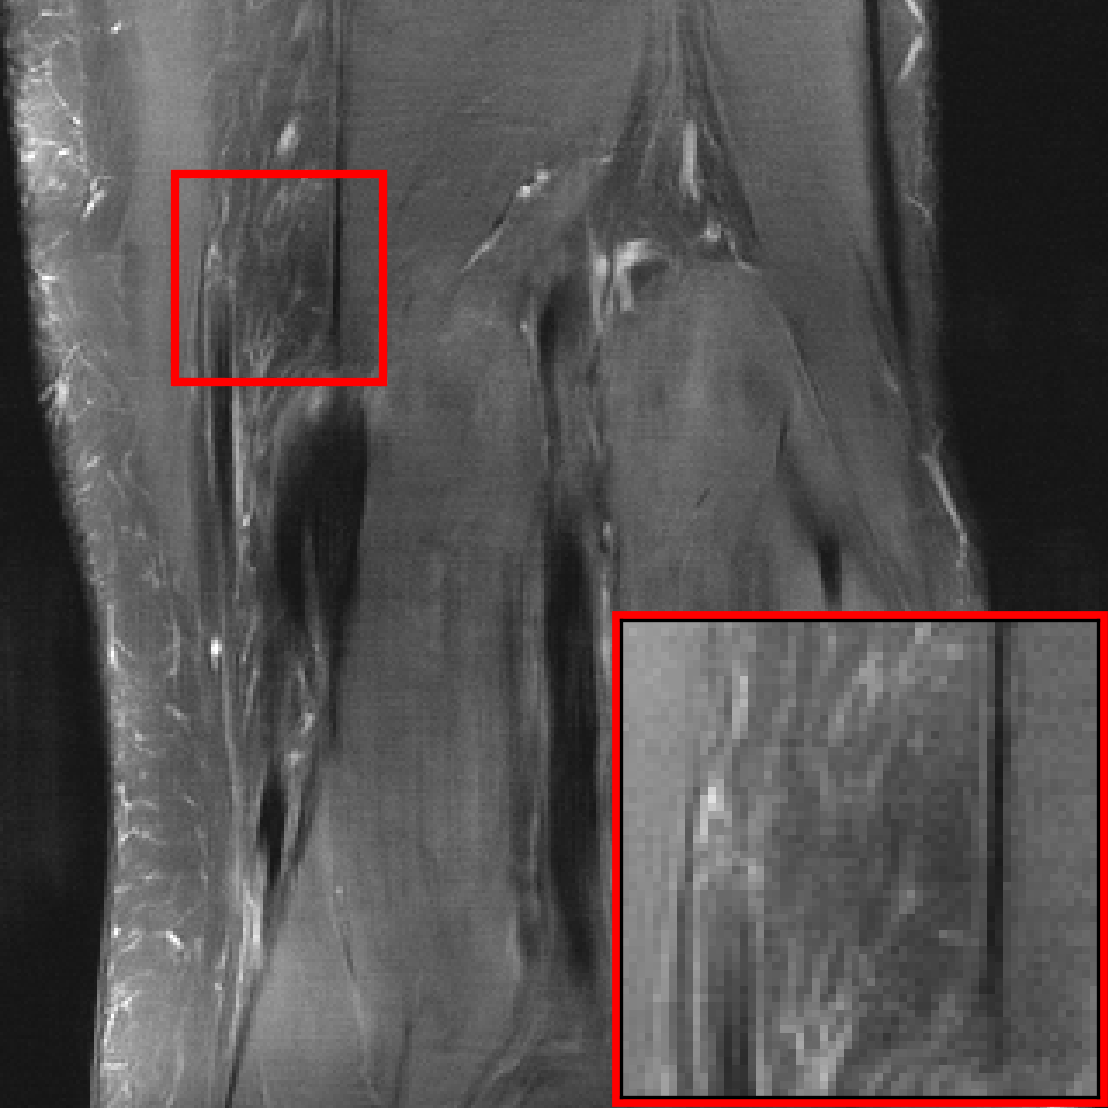

Appendix C Distribution-Shifts Induced by Changes of the Forward Model

In the main body, we considered distribution-shifts primarily related to the images, such as different contrast and anatomies. In this section, we consider two distribution-shifts that are induced by changes of the forward model, i.e., the relation of measurements and object to be imaged. We consider shifts in the acceleration factor and a distribution-shift related to the number of coils.

C.2 Distribution-Shifts Related to Number of Receiver Coils

We now consider a shift in the number of receiver coils. For distribution , we select all knees scans collected with the 6 different combinations of image contrasts and scanners (see Figure 2). All knee scans are collected with 15 coils. For distribution , we select the brain scans from the scanner Avanto since measurements from this scanner are collected with 4 coils.

For this distribution-shift we noticed that models, in particular VarNet which estimates sensitivity maps, struggles to accurately predict the mean value of the images resulting in a noticeable drops in SSIM. However, this degradation was hardly noticeable when looking at the reconstructions. Given that radiologists routinely adjust the brightness and contrast of MRI images during inspection through a process known as windowing \citepishidaDigitalImageProcessing1984, we normalize the model output and target to have the same mean and variance during evaluation. The results are depicted in Figure 14, where we see that training on a diverse set increases effective robustness on this distribution-shift.